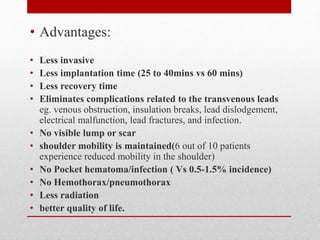

The document discusses leadless pacemakers as an alternative to traditional transvenous pacemakers. It provides a brief history of pacemakers and then describes the key advantages of leadless pacemakers as being less invasive, having a shorter procedure time and recovery period, and eliminating complications related to transvenous leads. It summarizes the results of clinical trials showing the safety and efficacy of implanting leadless pacemakers, with high implant success rates and low complication rates similar to traditional pacemakers.